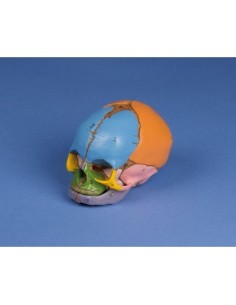

3B Scientific - Mini-modèle anatomique du crâne, en 3 parties A18/15

Crâne classique transparent, séparable en 3 parties, modèle anatomique 3B Scientific A20/T

Crâne avec gnathoschisis et fente palatine, modèle 3B Scientific A29/3

3B scientifique, enseignement de luxe crâne BONElike™A283